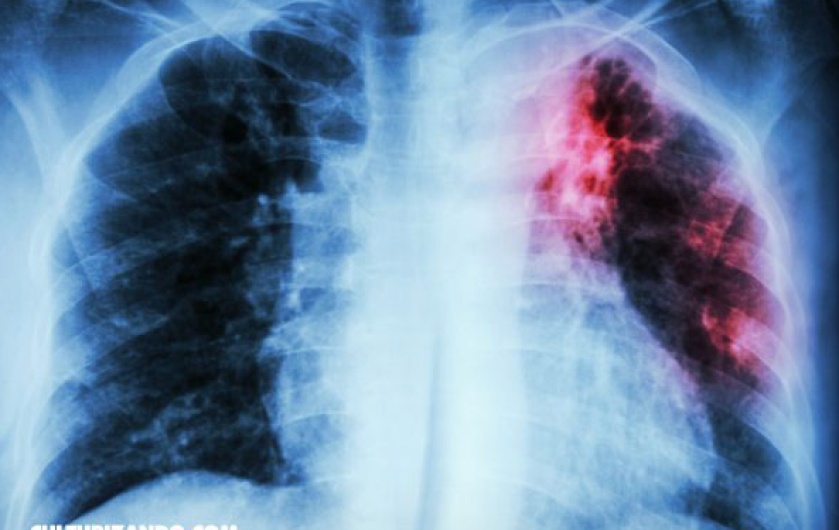

En lo que va del año, se han registrado un total de 48 casos nuevos de personas portadoras de Tuberculosis, de acuerdo con el departamento de Microbacteriosis de la Jurisdicción Sanitaria 5.

“En cuanto a menores de edad afectados por Tuberculosis oscilan entre los 15 y 19 años de edad, más un niño de 5 años que está a través del tratamiento binacional, las personas que tengan más de quince días con tos y flemas, deben realizarse el examen para descartar si es tuberculosis” indicó González Arrambide.